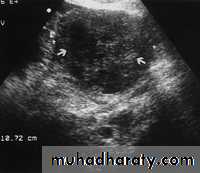

Premature ovarian failure.

Ultrasonography in Gynaecology

Image from a woman in premature ovarian failure. Only the stroma of the ovary is identified. A very few follicles of less than 1 mm diameter can be observed on the inferior aspect of the ovary.